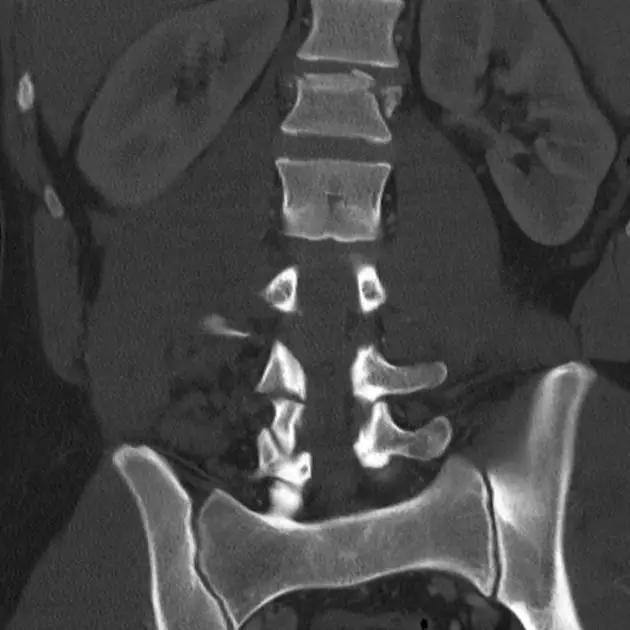

脊柱骨折

1. Burst 骨折

椎体轴向压力造成的骨折,通常发生骨折碎片向外侧的移位。可以发生在颈椎、胸椎或腰椎。

(来源:Radiopaedia)